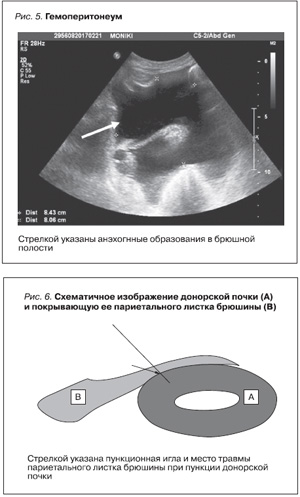

В данном случае произошло казуистическое осложнение – кровотечение в брюшную полость после транскутанной тонкоигольной биопсии трансплантата. Источником кровотечения стали место пункции трансплантата и дефект париетального листка брюшины, покрывающий трансплантат, через который выполнена биопсия. Хотя биопсия выполнена под контролем УЗИ, не была дифференцирована брюшина, предлежащая к трансплантату. Необходимо отметить, что из 253 биопсий, выполненных в нашем центре, такого рода осложнение встретилось впервые (0,39%). Практически все биопсии трансплантата выполнены одним нефрологом, прошедшим соответствующий курс обучения. В случае кровотечения в паранефральную клетчатку трансплантата гематома, как правило, не распространяется на большом пространстве, т.к. паранефральная клетчатка на большом протяжении интимно спаяна с трансплантированной почкой. Спаечный процесс не дает распространяться гематоме. И сама гематома в случае образования сдавливает место пункции и останавливает кровотечение. При проникновении пункционной иглы в синус почки или лоханку такого сдавления нет и кровотечение возникает по мочевым путям. В нашем случае ранение париетального листка брюшины свело на нет сдавливающий гематомой момент и кровь свободно, через дефект брюшины стала проникать в брюшную полость. И несмотря на то что у больной не было коагулопатии, (коагулограмма в пределах нормы), по-видимому, произошло ранение крупной сегментарной артерии трансплантата во время биопсии и кровь свободно стала поступать как в паранефральное пространство, так и в брюшную полость. Избежать это осложнение возможно, тщательно дифференцируя все образования в месте допустимой пункции донорской почки. Своевременная диагностика кровотечения в брюшную полость и ликвидация осложнения позволили спасти не только жизнь больной, но и трансплантат. Несмотря не то что транскутанная биопсия считается безопасной процедурой как собственных, так и трансплантированных почек, в очень редких случаях эта процедура может также приводить к нефрэктомии и даже к смерти [7, 19]. Макро- или микрогематурии являются основным осложнением пункционной биопсии. Она может возникать на различных уровнях: